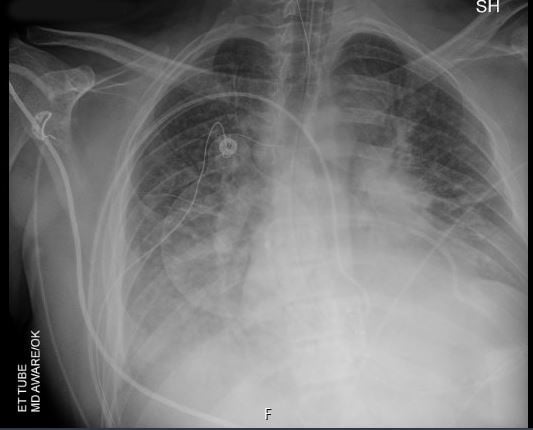

A 30-year-old man presents with dyspnea and is found to have an anterior mediastinal mass, as well as supraclavicular lymphadenopathy; biopsy of the mass is consistent with thymic carcinoma. Imaging shows his anterior mediastinal mass, lung and diaphragmatic lesions consistent with metastatic malignancy, and probable pericardial involvement with small pericardial effusion (Figures 1, 2, 3, and 4).

Fig. 5: Chest radiograph prior to pericardiocentesis. -